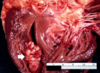

Arrow: adherent thrombi at the apex of (L) ventricle

what is this?